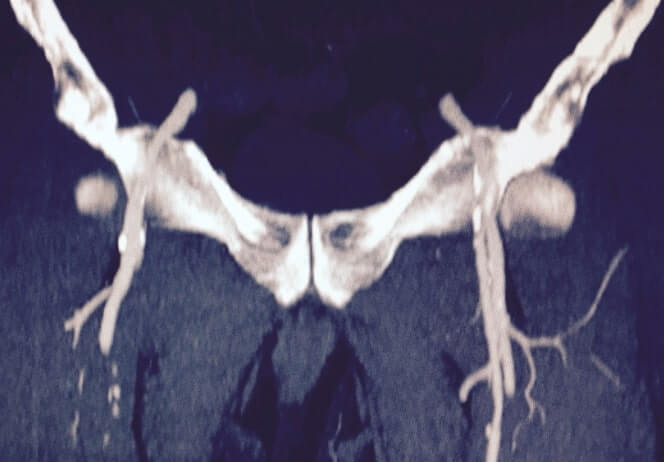

La enfermedad arterial es la principal causa de amputaciones no traumáticas……. Sus principales causas son la diabetes y el tabaquismo. En esta angiotomografía se observan las múltiples lesiones desde la aorta abdominal hasta distal, siendo más evidente a nivel de la arteria poplítea (a nivel de la rodilla hasta los pies).